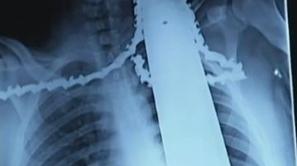

Svet Motorka se mu je zarila v ramo in vrat 21-letni delavec se je ponesrečil z motorno žago, ki je pristala v njegovi rami in vratu.